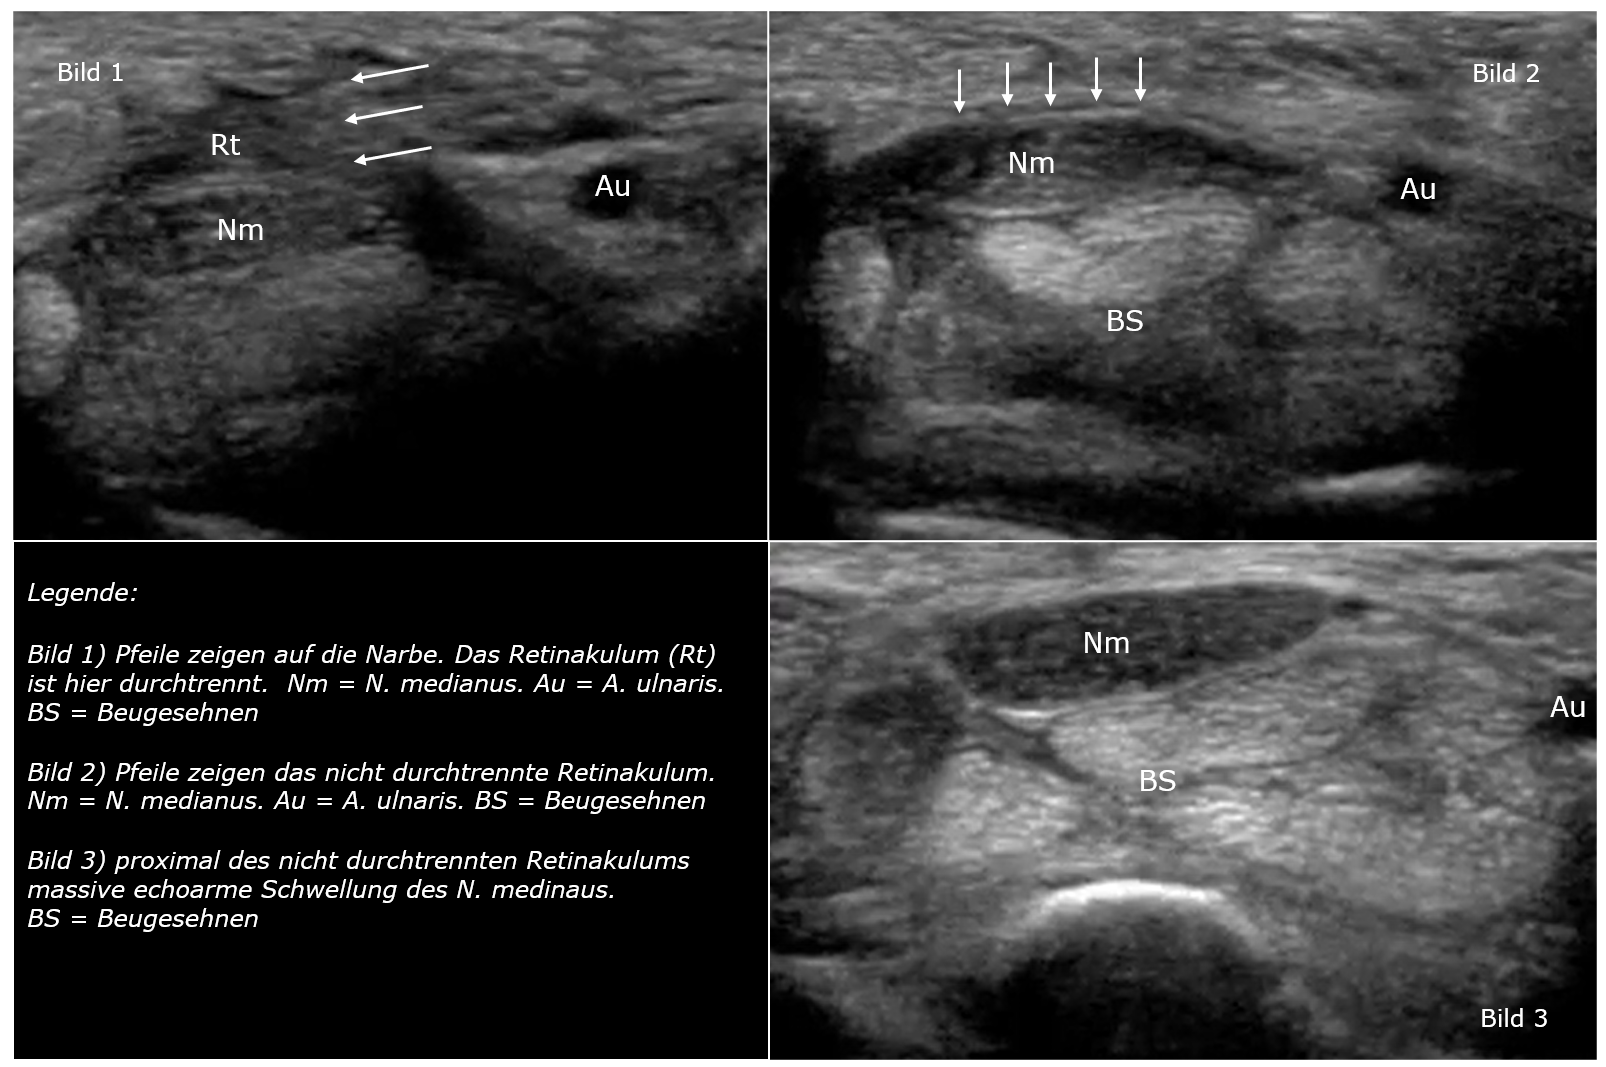

Im proximalen Karpaltunnel zeigte sich, dass das Karpalband (Retinaculum flexorum) nicht durchgetrennt war (Bild 1). Darüber hinaus bestand eine massive Schwellung des N. medianus proximal dieser Stelle. Weiter distal war das Retinakulum durchgetrennt (Bild 2). Das Video zeigt zunächst den Ausgangsbefund mit dem nicht durchgetrennten Retinakulum im proximalen Karpaltunnel. Dann wird die Schallsonde nach distal bewegt und die Spaltung dargestellt. Daraufhin wird die Sonde zurück in Richtung Unterarm bewegt. Es lässt sich eine massive Nervenschwellung darstellen. Am Ende des Videos ist der Nerv etwa 2 cm proximal der Handgelenksfalte wieder normal.

Legende zu den Abbildungen:

1. Intaktes Retinakulum (Pfeile) im proximalen Karpaltunnel. Nm= N. medianus; au = A. ulnaris; nu = N. ulnaris; sc = Os scaphoideum ; fcr = Sehne des M. flexor carpi radialis ; fpl = Sehne des M. flexor pollicis longus ; fds 2-4 = Sehnen des M. flexor digitorm superficialis zu den Fingern 2-4 ; fdp2 = Sehne des M. flexor digitorum profundus

2. Spaltung des Retinakulums (Pfeil) im proximalen Karpaltunnel. N = N. medianus